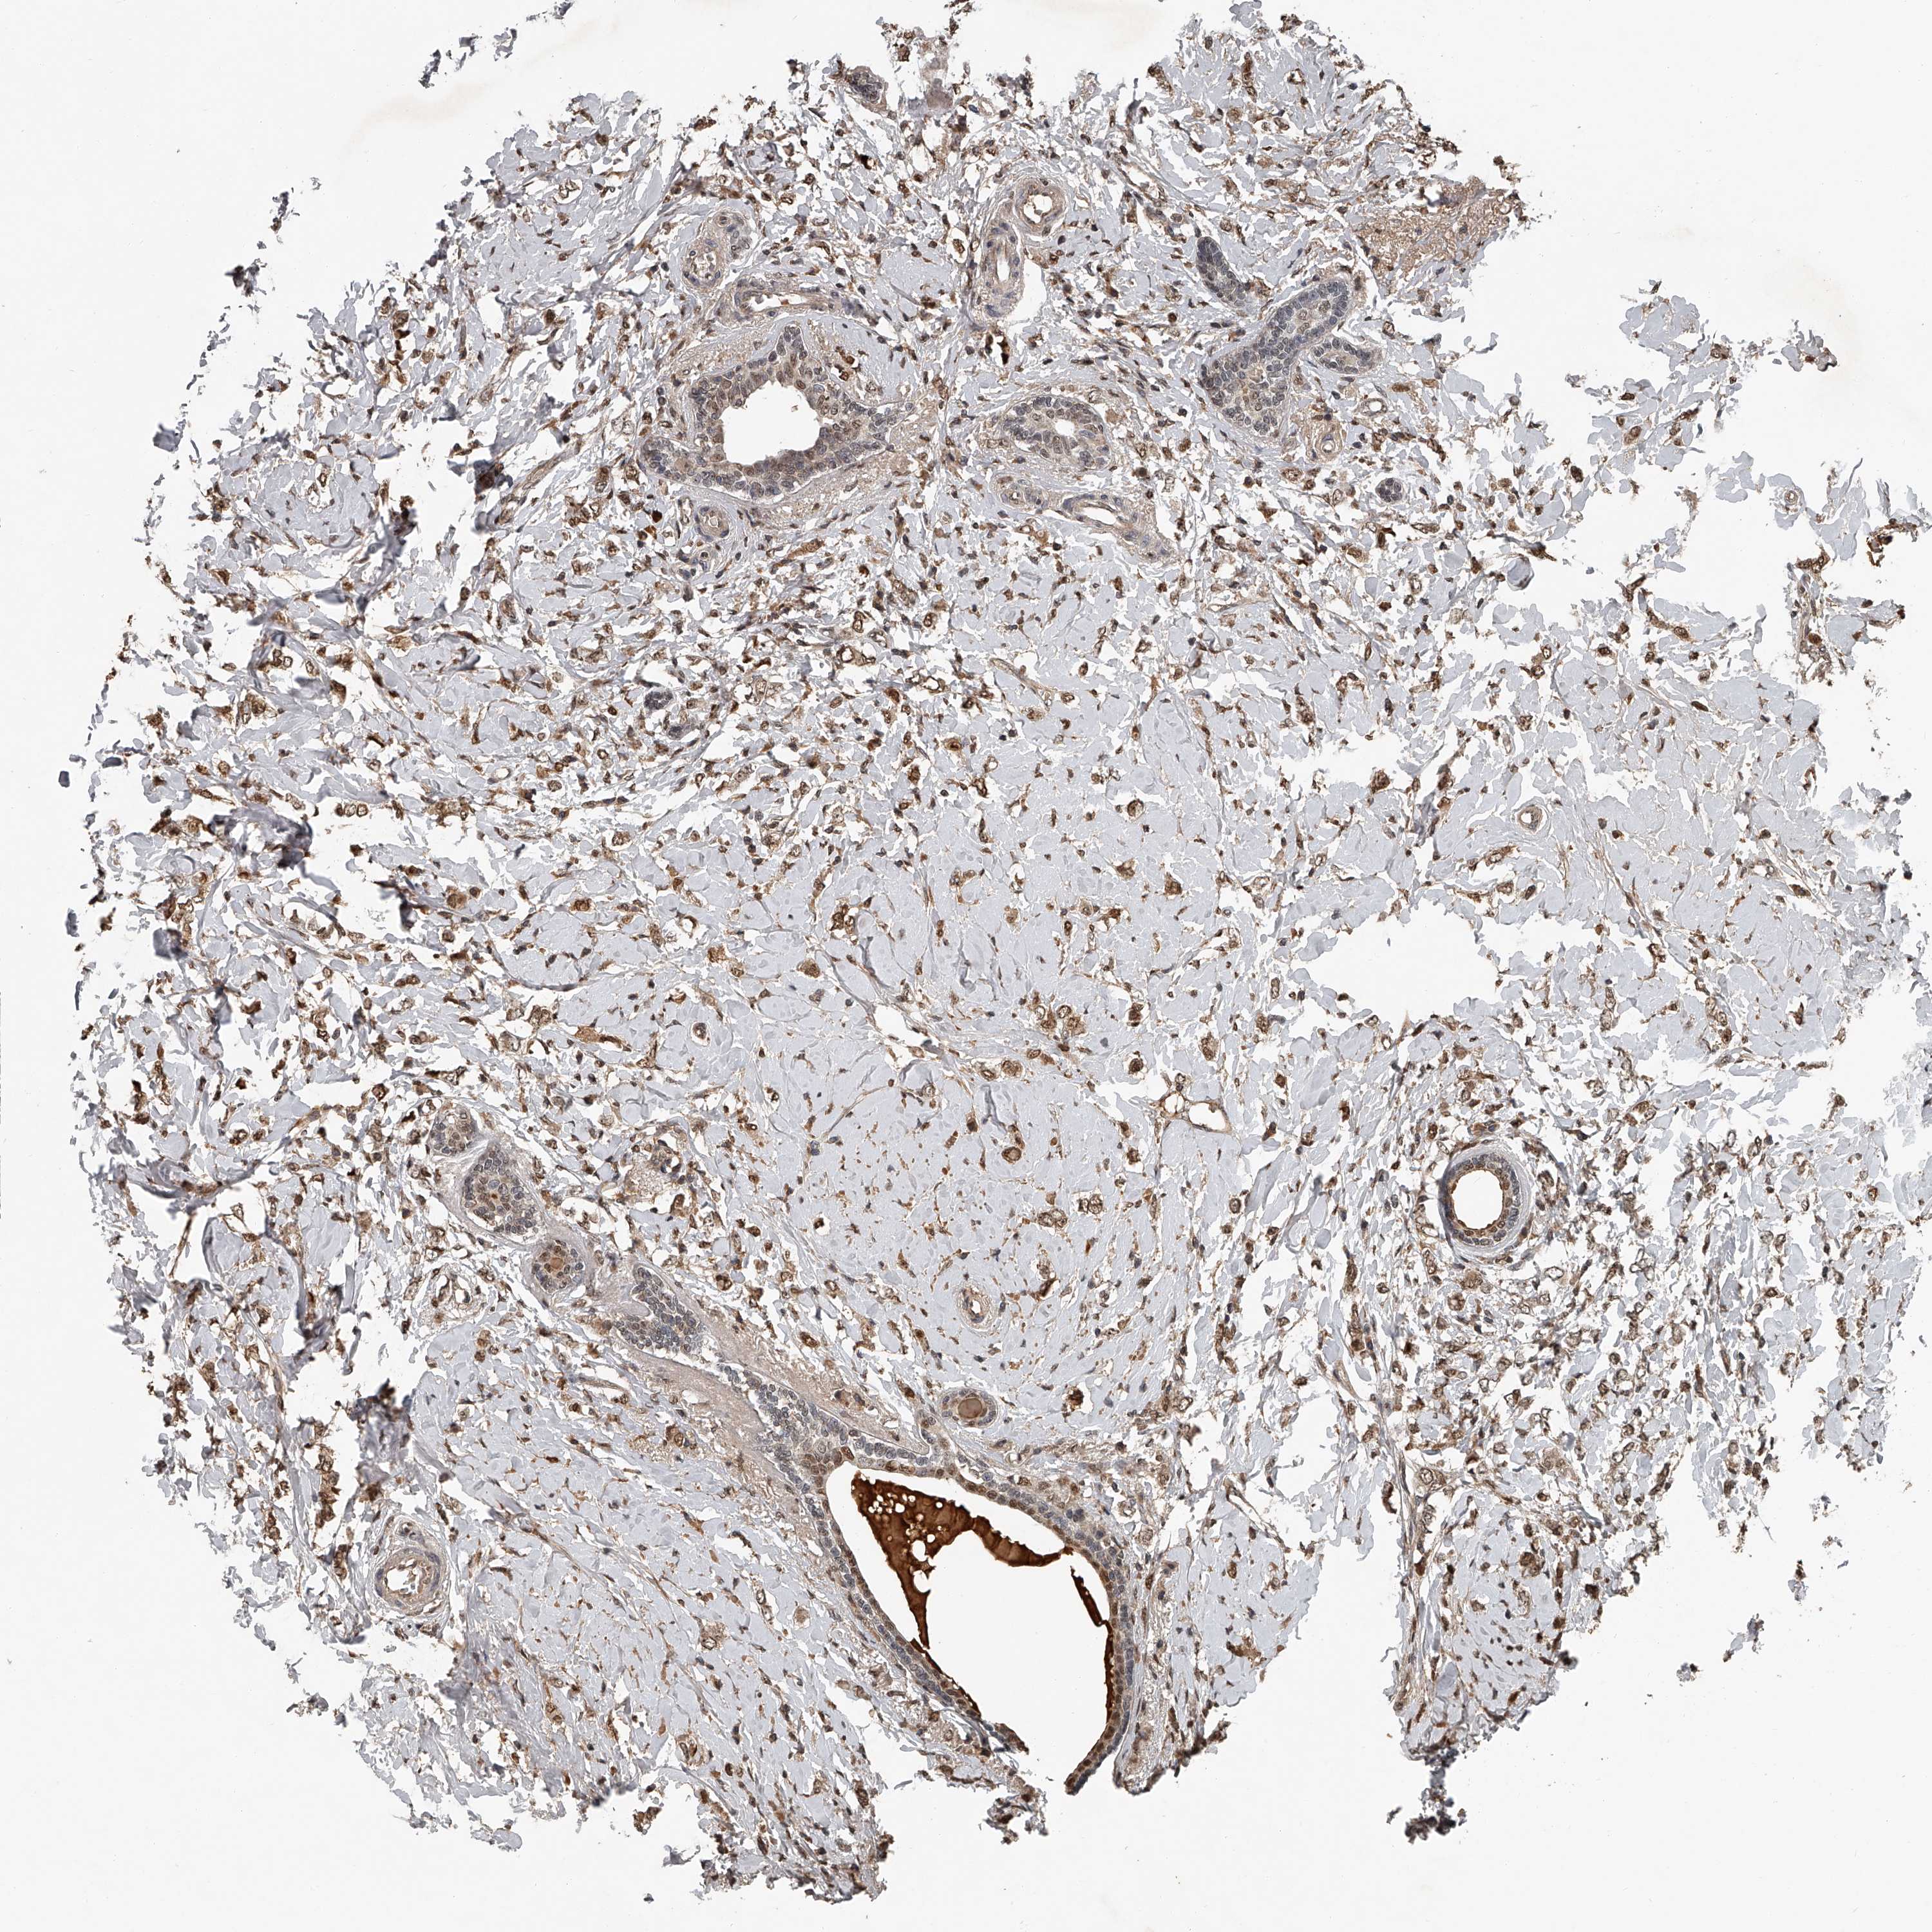

CANCER BREAST CANCER Show tissue menu

Breast cancer

Human cancer

Breast invasive carcinoma